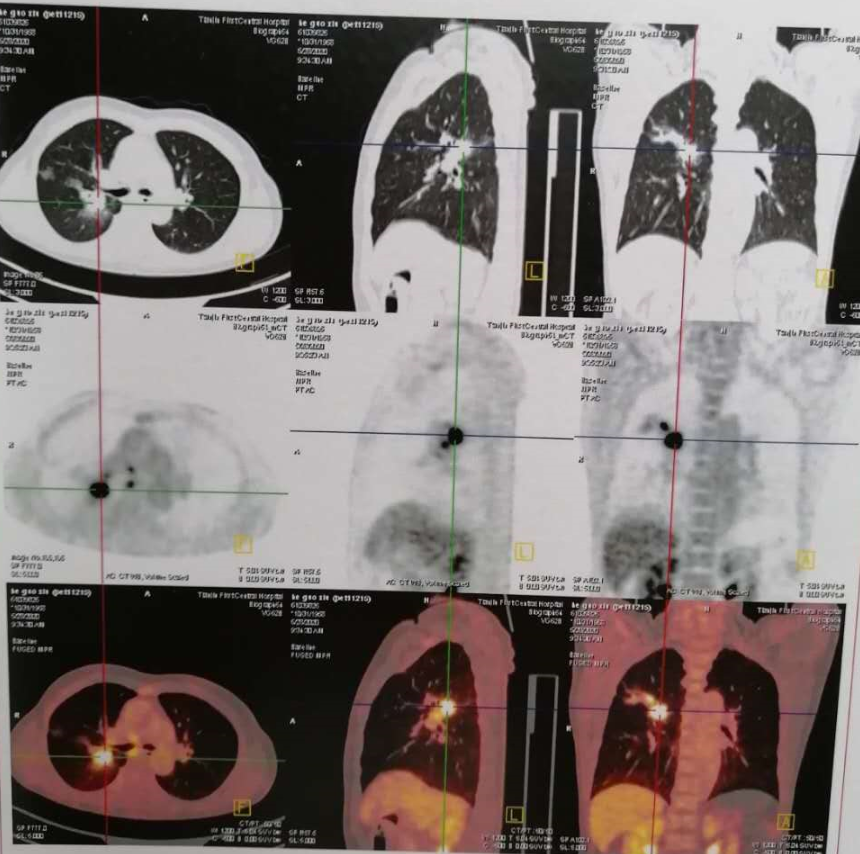

PET-CT:

右肺上叶多发结节(2.3*2.0*2.1cm),周围伴多发磨玻璃密度灶,跨叶尖裂生长,代谢异常增高,考虑恶性;

-

右侧肺门及纵隔内(血管前,气管前,隆突下)多发肿大淋巴结,代谢异常增高,考虑恶性。

双侧髂骨PET-CT显像可见放射性浓聚,考虑转移。